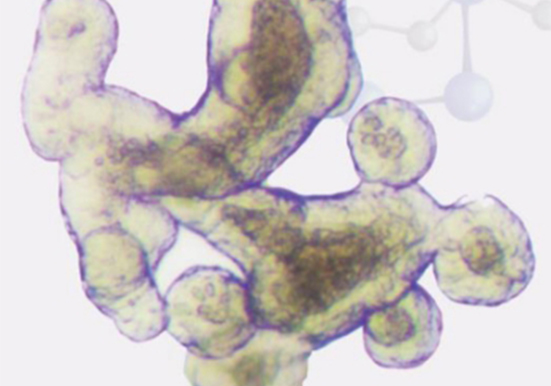

类器官明场图片展示

55.png